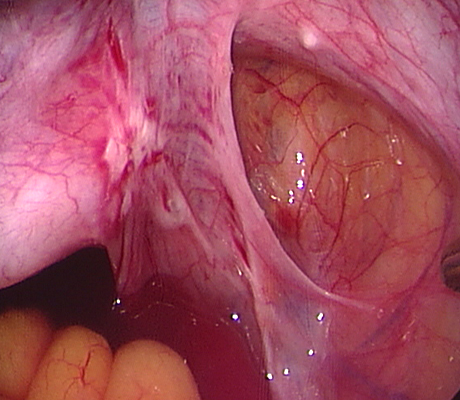

Endometriosis is a non-cancerous condition where the endometrial tissue or womb lining which normally grows only in the uterus is found in other parts of your pelvis, for example the ovaries, fallopian tubes, rectum, bladder, appendix and pelvic walls. This womb lining that grows outside the uterus responds also to hormones but at the time of your periods it can not be expelled (as the womb lining) and causes pain, cysts in the ovaries (called chocolate cysts), inflammation in your pelvis, scar tissue, pain with sexual intercourse, chronic pelvic pain, pain when passing bowel motions, lower backache, symptoms similar to urinary tract infections, premenstrual discomfort, etc.

Diagnosis of endometriosis can only be done with certainty through a laparoscopy. Although this means surgery, a patient can also be treated at the same time, saving an extra procedure and the associated risks.

Laparoscopy is an operation (keyhole surgery) conducted under general anaesthesia. A telescope is introduced into a small incision in your navel, other small incisions are made for using special laparoscopic instruments and all the pelvic organs are examined with magnification (Video-laparoscopy) ; then the endometriosis is treated. Video Laparoscopy allows conservative surgery (hysterectomy is NOT the usual treatment for endometriosis) which means laparoscopic excision of the endometriotic implants, with restoration of the normal anatomy and preservation of the uterus, tubes and ovaries.